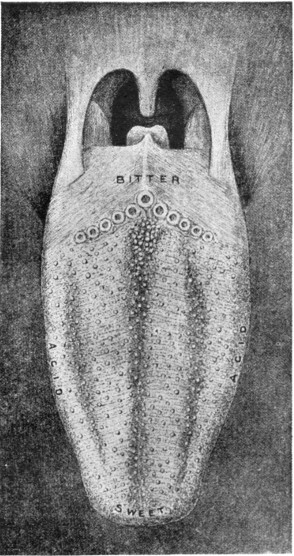

ITS STRUCTURE—ORGANIZATION INTO SYSTEMS—FUNCTIONS—SPECIAL SENSES—NERVOUS SYSTEM—PERSONAL HYGIENE—PREVENTION OF DISEASE—INTERDEPENDENCE OF BODY AND MIND—EUGENICS—ILLUSTRATIONS AND CHARTS.